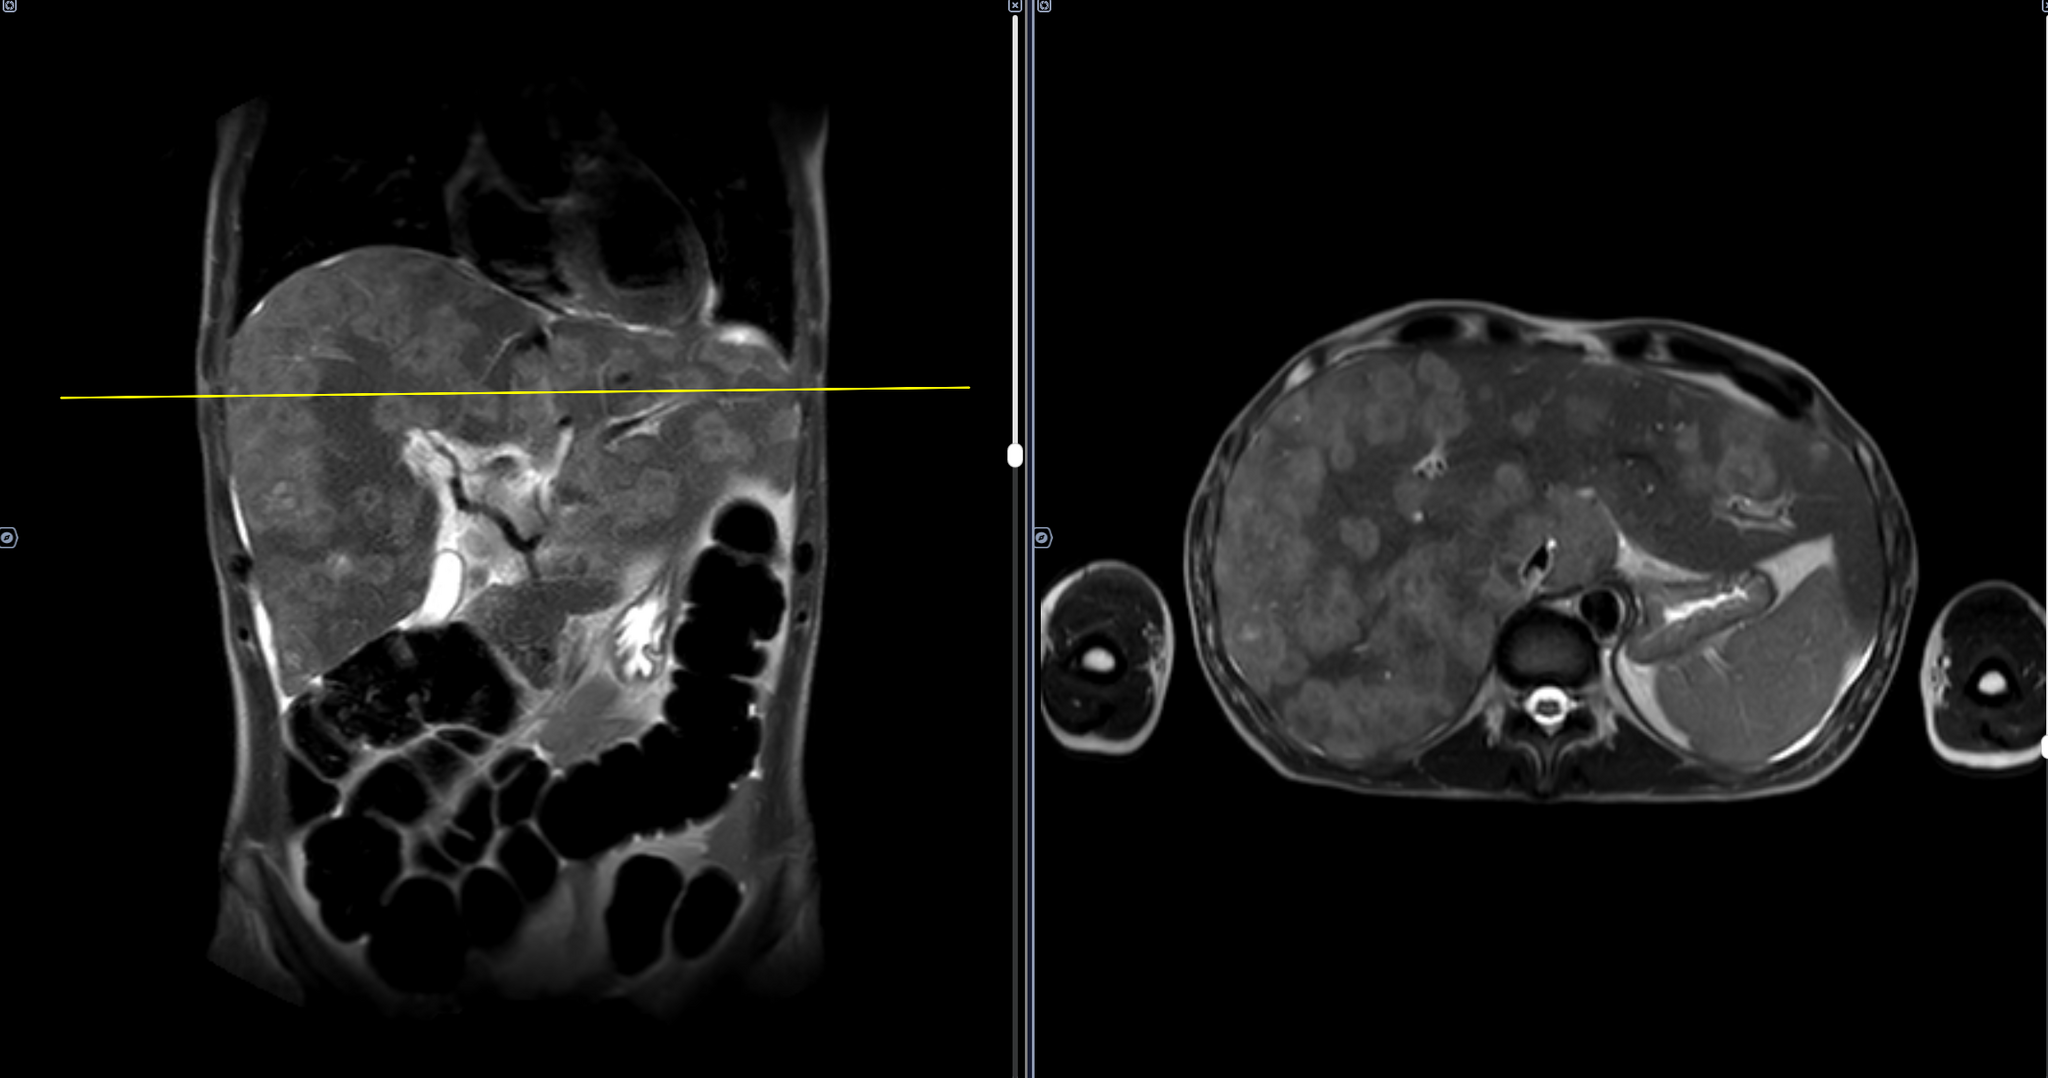

Печень увеличена. МР-сигнал от паренхимы печени изменен на фоне неоднородной структуры за счет наличия во всех сегментах многочисленных разных размеров очагов повышенного мр-сигнала по Т2, пониженного по Т1, с ограничением диффузии. С учетом предоставленного анамнеза, выявленные изменения можно трактовать, как проявление оппортунистической инфекции. Заключение: МР-картина изменений, характерных для оппортунистической инфекции печени на фоне гепатомегалии